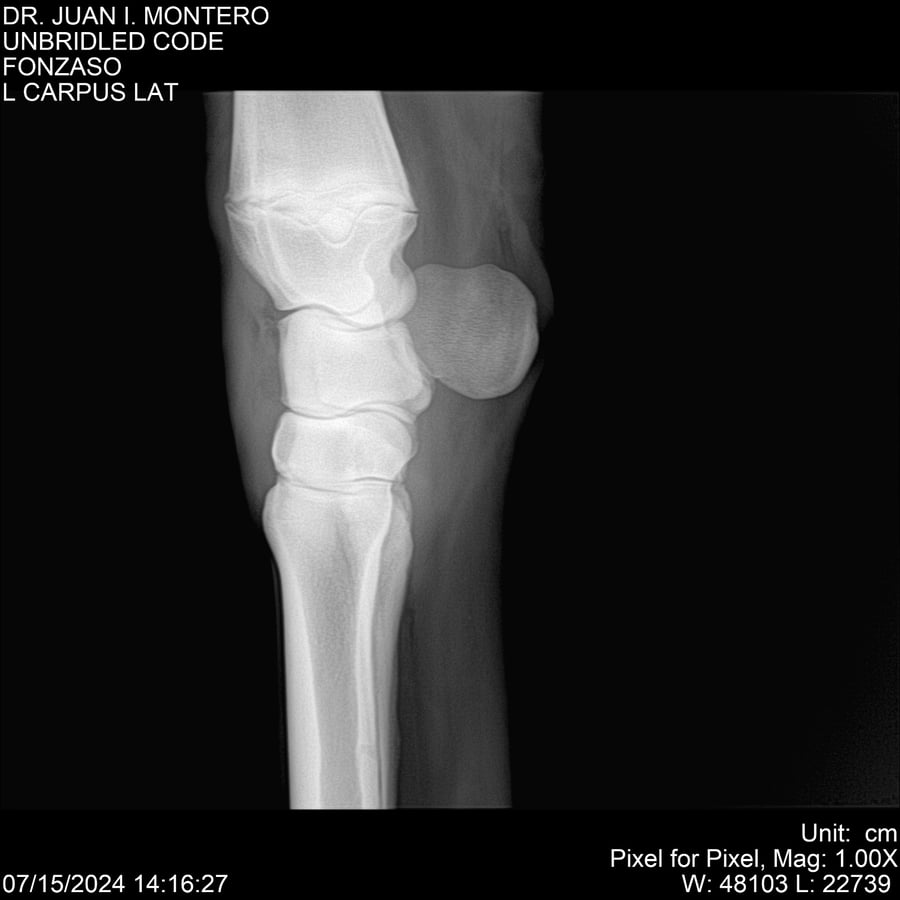

• Empresa: Abelenda N. R., Walter Hugo